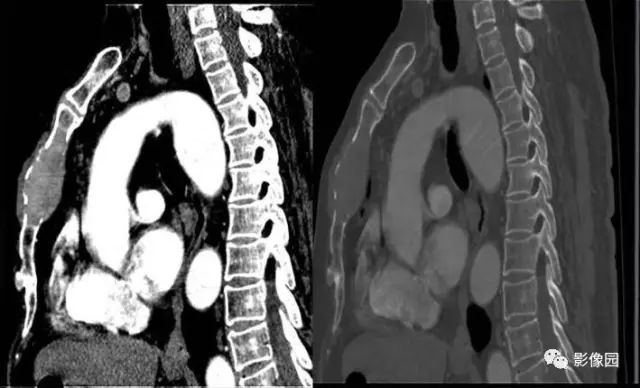

肚肚丫头: 胸骨体局部呈膨胀性骨质吸收破坏,内呈软组织密度影,可见点状钙化,增强扫描呈轻度强化,周围软组织略肿胀。考虑:1.骨巨细胞瘤;2.浆细胞瘤;3.嗜酸性肉芽肿

CT表现:特征性穿凿状、鼠咬状及蜂窝状骨破坏,边缘清楚,骨质疏松,病理性骨折及软组织肿块等表现,骨质硬化及骨膜反应少见。

骨破坏区完全为软组织取代,骨质膨胀,边界清楚,常突破骨皮质形成软组织肿块。增强扫描可见病灶轻中度强化,一般于静脉期达峰值。